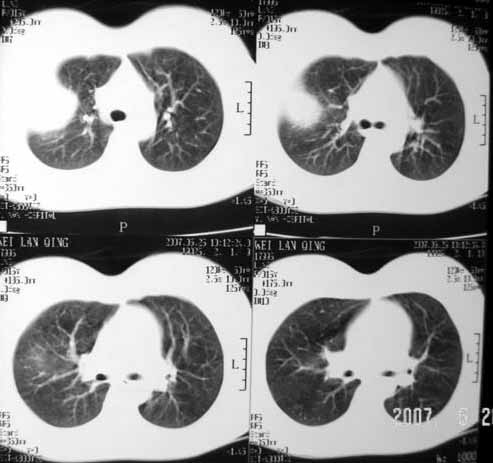

[br]病灶定位在肋骨上,原因如图[br]定性支持邓老师的动脉瘤样骨囊肿、骨纤[br]巨细胞瘤较少发生钙化,所以我不考虑[br]桨细胞瘤不会发生膨胀性改变吧,经验少期待老师们的指正[br]骨结核内大多有沙粒状钙化,所以可能性也不大

以下是引用qiuleiyu在2007-5-26 19:50:00的发言:[br]右第二肋腋侧呈明显膨胀性、分叶状改变,内无明显间隔,ct值49hu,病变大小约67x57mm,周围硬化缘无断裂,内缘见多数骨嵴,肿块与正常骨间界限清楚。无移行带。周围软组织无浸蚀,胸膜腔无积液。[br]结合年龄考虑:1、右第二肋动脉瘤样骨囊肿可能性大;[br] 2、需同骨巨细胞瘤、骨纤鉴别。